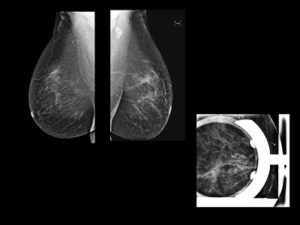

1. Irregular mass with spiculations and microcalcifications in supra-areolar region of left breast – BIRADS 5. 2. On MRI – Irregular enhancing mass with surrounding extensive clumped and nodular enhancement in ductal distribution in upper quadrant- representing multifocal DCIS or extensive ductal spread. 3. Thickening in left axillary lymph nodes- likely metastaticCortical

1. Invasive ductal carcinoma with multifocal DCIS / extensive intraductal spread. 2. MRI changes the management from Breast conserving surgery to MRM because of extensive intraductal component other then mass.